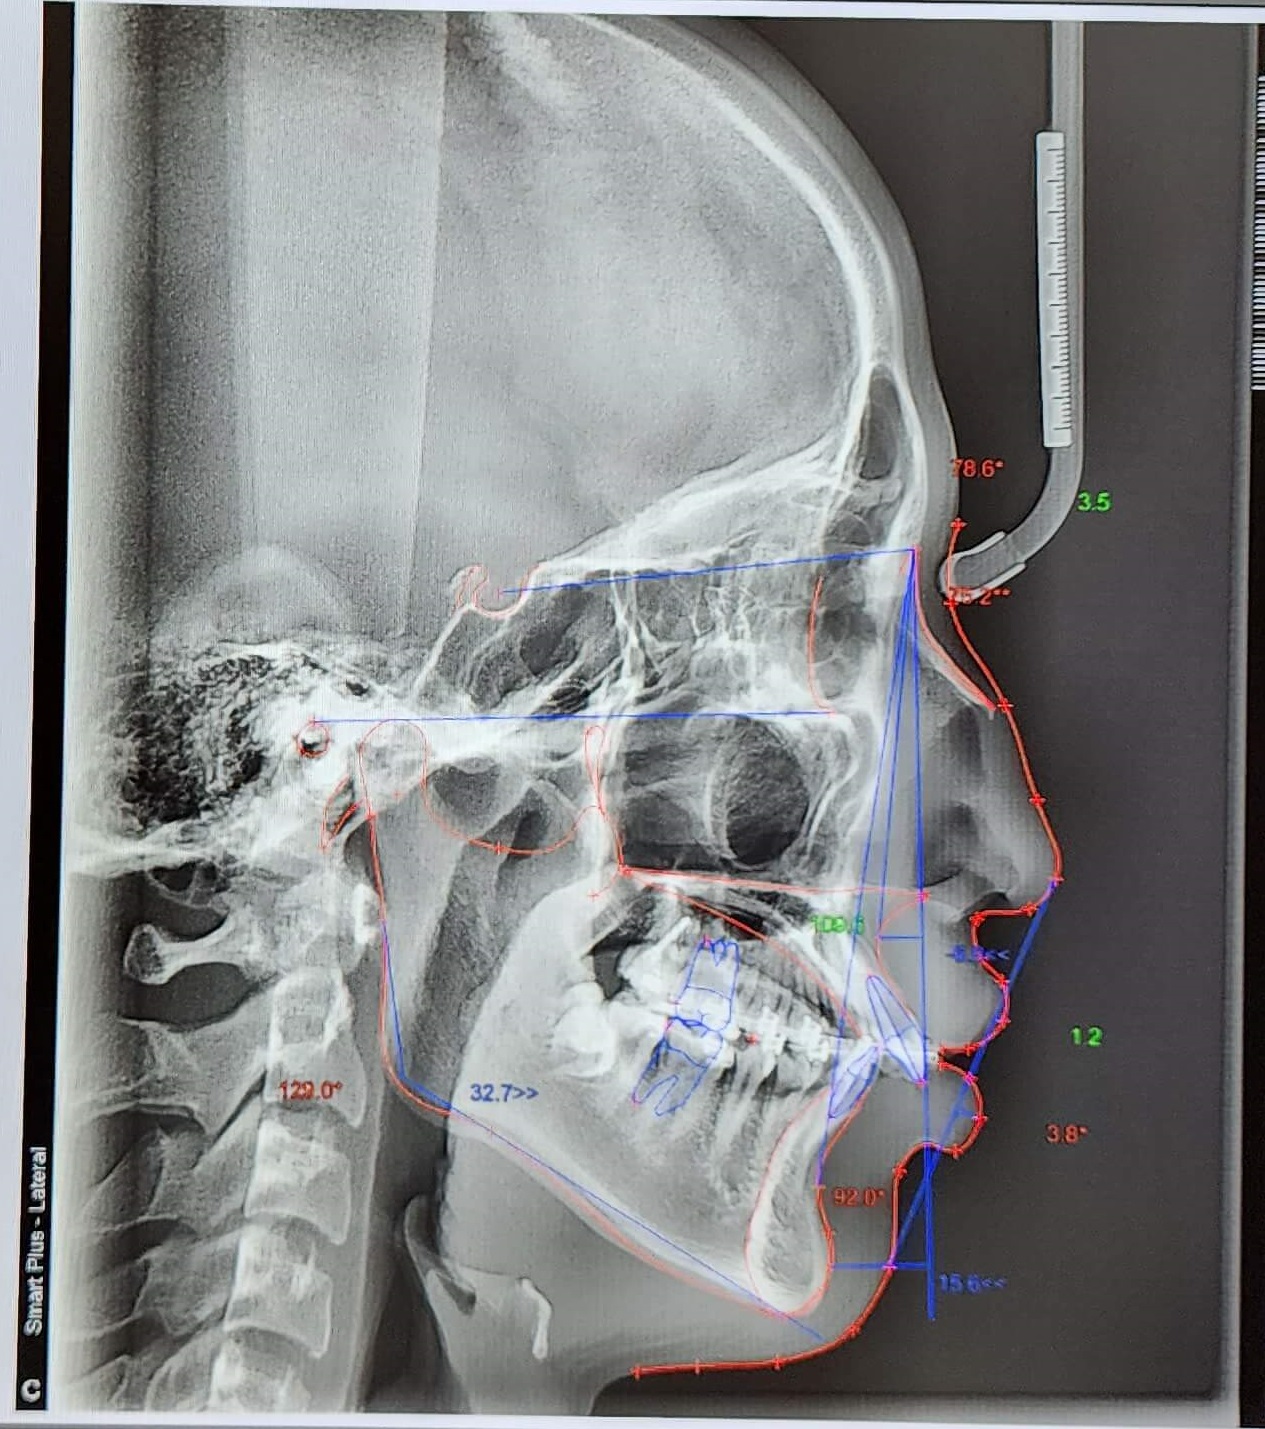

■ 정밀검사 2차 (5개월차)

전체 교정 브라켓을 부착 후 2달 정도 지나고 나니 S자로 휘어진 철사가 어느 정도 일자로 복원되면서 앞니의 치아배열이 가지런하게 정리가 되어있습니다.

이제부터 본격적인 장기레이스 정밀하게 교정에 들어가기 위해 2차 정밀 검사를 하게 되는데요. 좀 더 미관적으로 기능적으로 좋은 치료 방향을 잡기 검사를 하였습니다.

검사결과 발치여부의 선택이 있었고 발치를 하면 약간 튀어나온 입이 좀 더 보기 좋게 들어갈 수 있고 발치를 하지 않아도 크게 문제가 되지 않는다고 하였습니다.

발치로 인해 얻는 효과가 크지 않아 비발치로 선택하고 본격적인 교정에 들어갔습니다.

● 검사결과 내용

교정 진행과정은 순조롭게 진행이 잘되었으며 전체 교정기간 5개월 정도 지난 후 상태를 확인하였고 발치 후 교정, 비발치 교정의 선택만 하면 되었습니다.

위, 아래 발치 2개씩을 하면 치아공간이 생겨 좀 더 나은 교정이 될 수 있지만 비발치를 하여도 크게 문제가 되지 않기에 비발치를 선택하였습니다.

▼ 5개월 교정 후 사진(1)

▼ 5개월 교정후 사진(2)